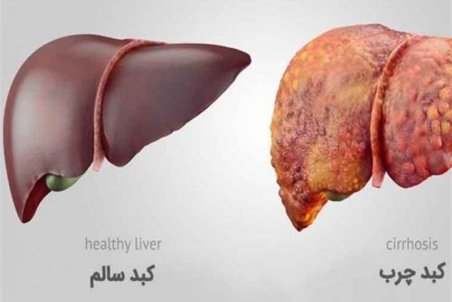

کبد چرب چیست؟؛ انواع،علت،علائم، درمان فوری و خانگی آن

کبد چرب به دلیل رسوب چربی ایجاد می شود.اطلاعاتی از کبد چرب چیست؟ گرید، علائم آن در زنان و مردان، روش تشخیص، درمان و مواد غذایی مفید و مضر آن را می خوانید.

با این نشانهها شما کبد چرب دارید

بیماری کبد چرب به معنی انباشت چربی در سلولهای کبد بوده البته طبیعی است که چربی در کبد داشته باشید، اما وقتی که چربی بیش از ۵ تا ۱۰ درصد در کبد وجود داشته باشد، در این صورت فرد به بیماری کبد چرب مبتلاست.

کبد ۲۰ درصد ایرانی ها چرب است/دومیلیون نفر گرفتار هپاتیت B و C

عضو پژوهشکده گوارش و کبد دانشگاه علوم پزشکی تهران، با اشاره به عارضه های هپاتیت، گفت: حدود ۲۰ درصد افراد جامعه مبتلا به کبد چرب هستند.

شیوع ۲۰ تا ۳۰ درصدی کبدچرب در ایران

یک فوق تخصص بیماریهای کبد و گوارش بالغین با اشاره به اجرای طرح "کبد سالم" در دانشگاه علوم پزشکی شهیدبهشتی، گفت: در مرحله اول این طرح، جمعیتی حدود ۱۰۰۰ نفر در شهر بومهن مورد آزمایش و غربالگری قرار خواهند گرفت و در ادامه این جمعیت تا ۵ هزار نفر نیز